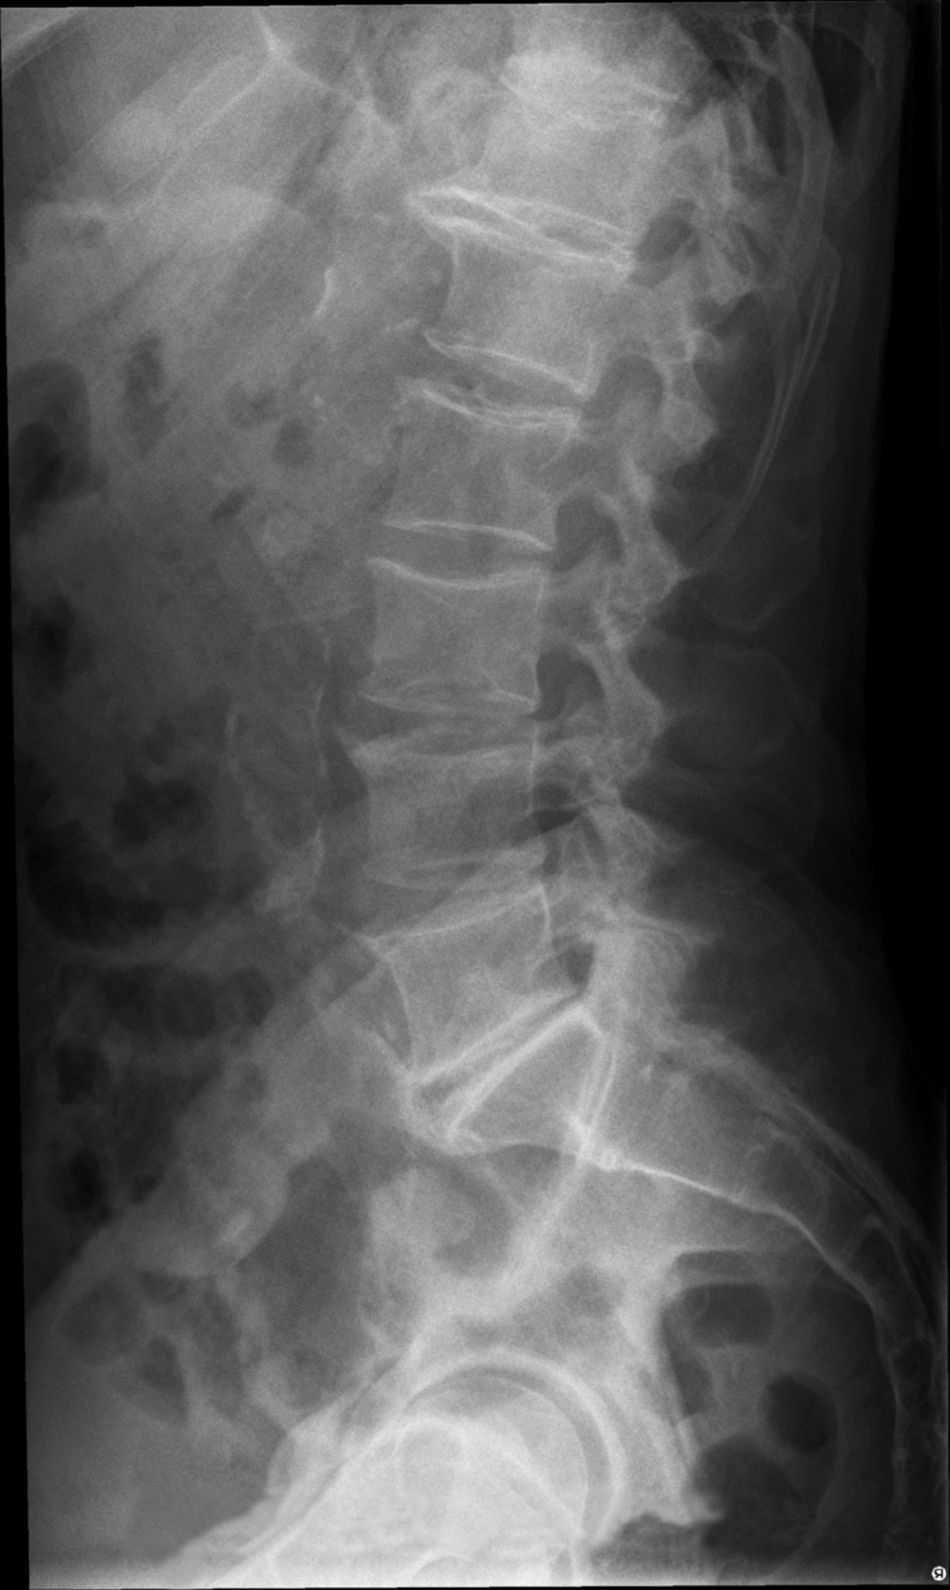

Rx Oblicua De Columna Lumbar

Rx oblicua de columna lumbar con pinzamiento y degeneración de las

Rx Oblicua De Columna Lumbar. Webcomo estudiante mostrar el posicionamiento de Rx columna lumbar WebUna radiografía de la columna lumbosacra es una imagen de los pequeños huesos (vértebras) en la parte baja de la columna. Esta zona incluye la región lumbar y el.

WebProyección lumbar AP. INDICACIONES. puede padecer de diferentes patologías principalmente degenerativas, como lo son las hernias discales lumbares,,. WebMuestra los huesos o vértebras de la parte baja de la columna, que incluye la región lumbar y el sacro y el área que conecta la columna a la pelvis de manera oblicua del lado.